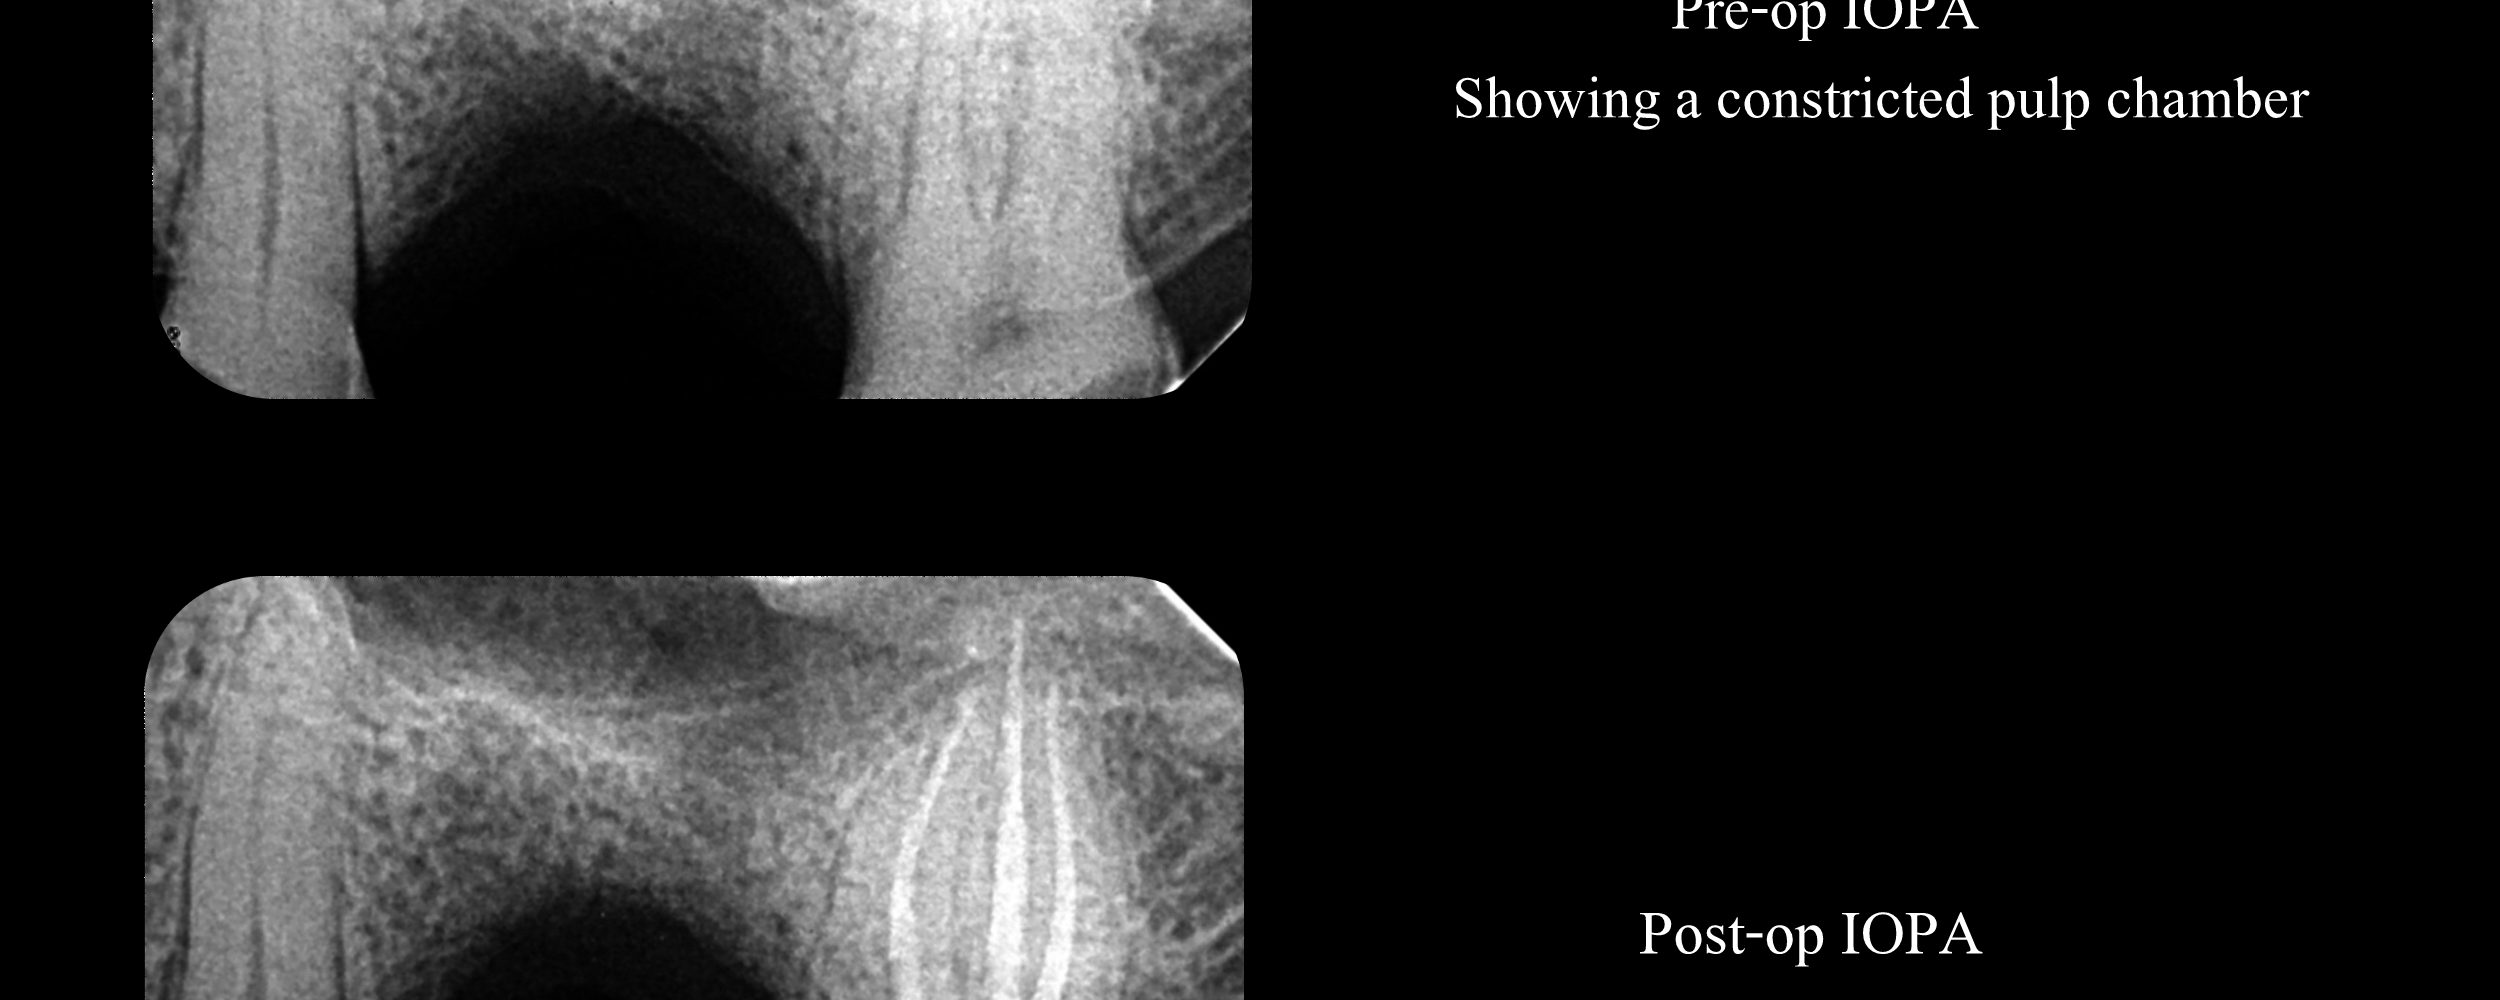

#15 Pulpitis – Canal Projection

Pre-op Assessment: Severe attrition and a constricted pulp chamber. Treatment plan: Access cavity planned taking into account the regression of the pulp chamber size. Canals shaped through the angles the canals project centrally.